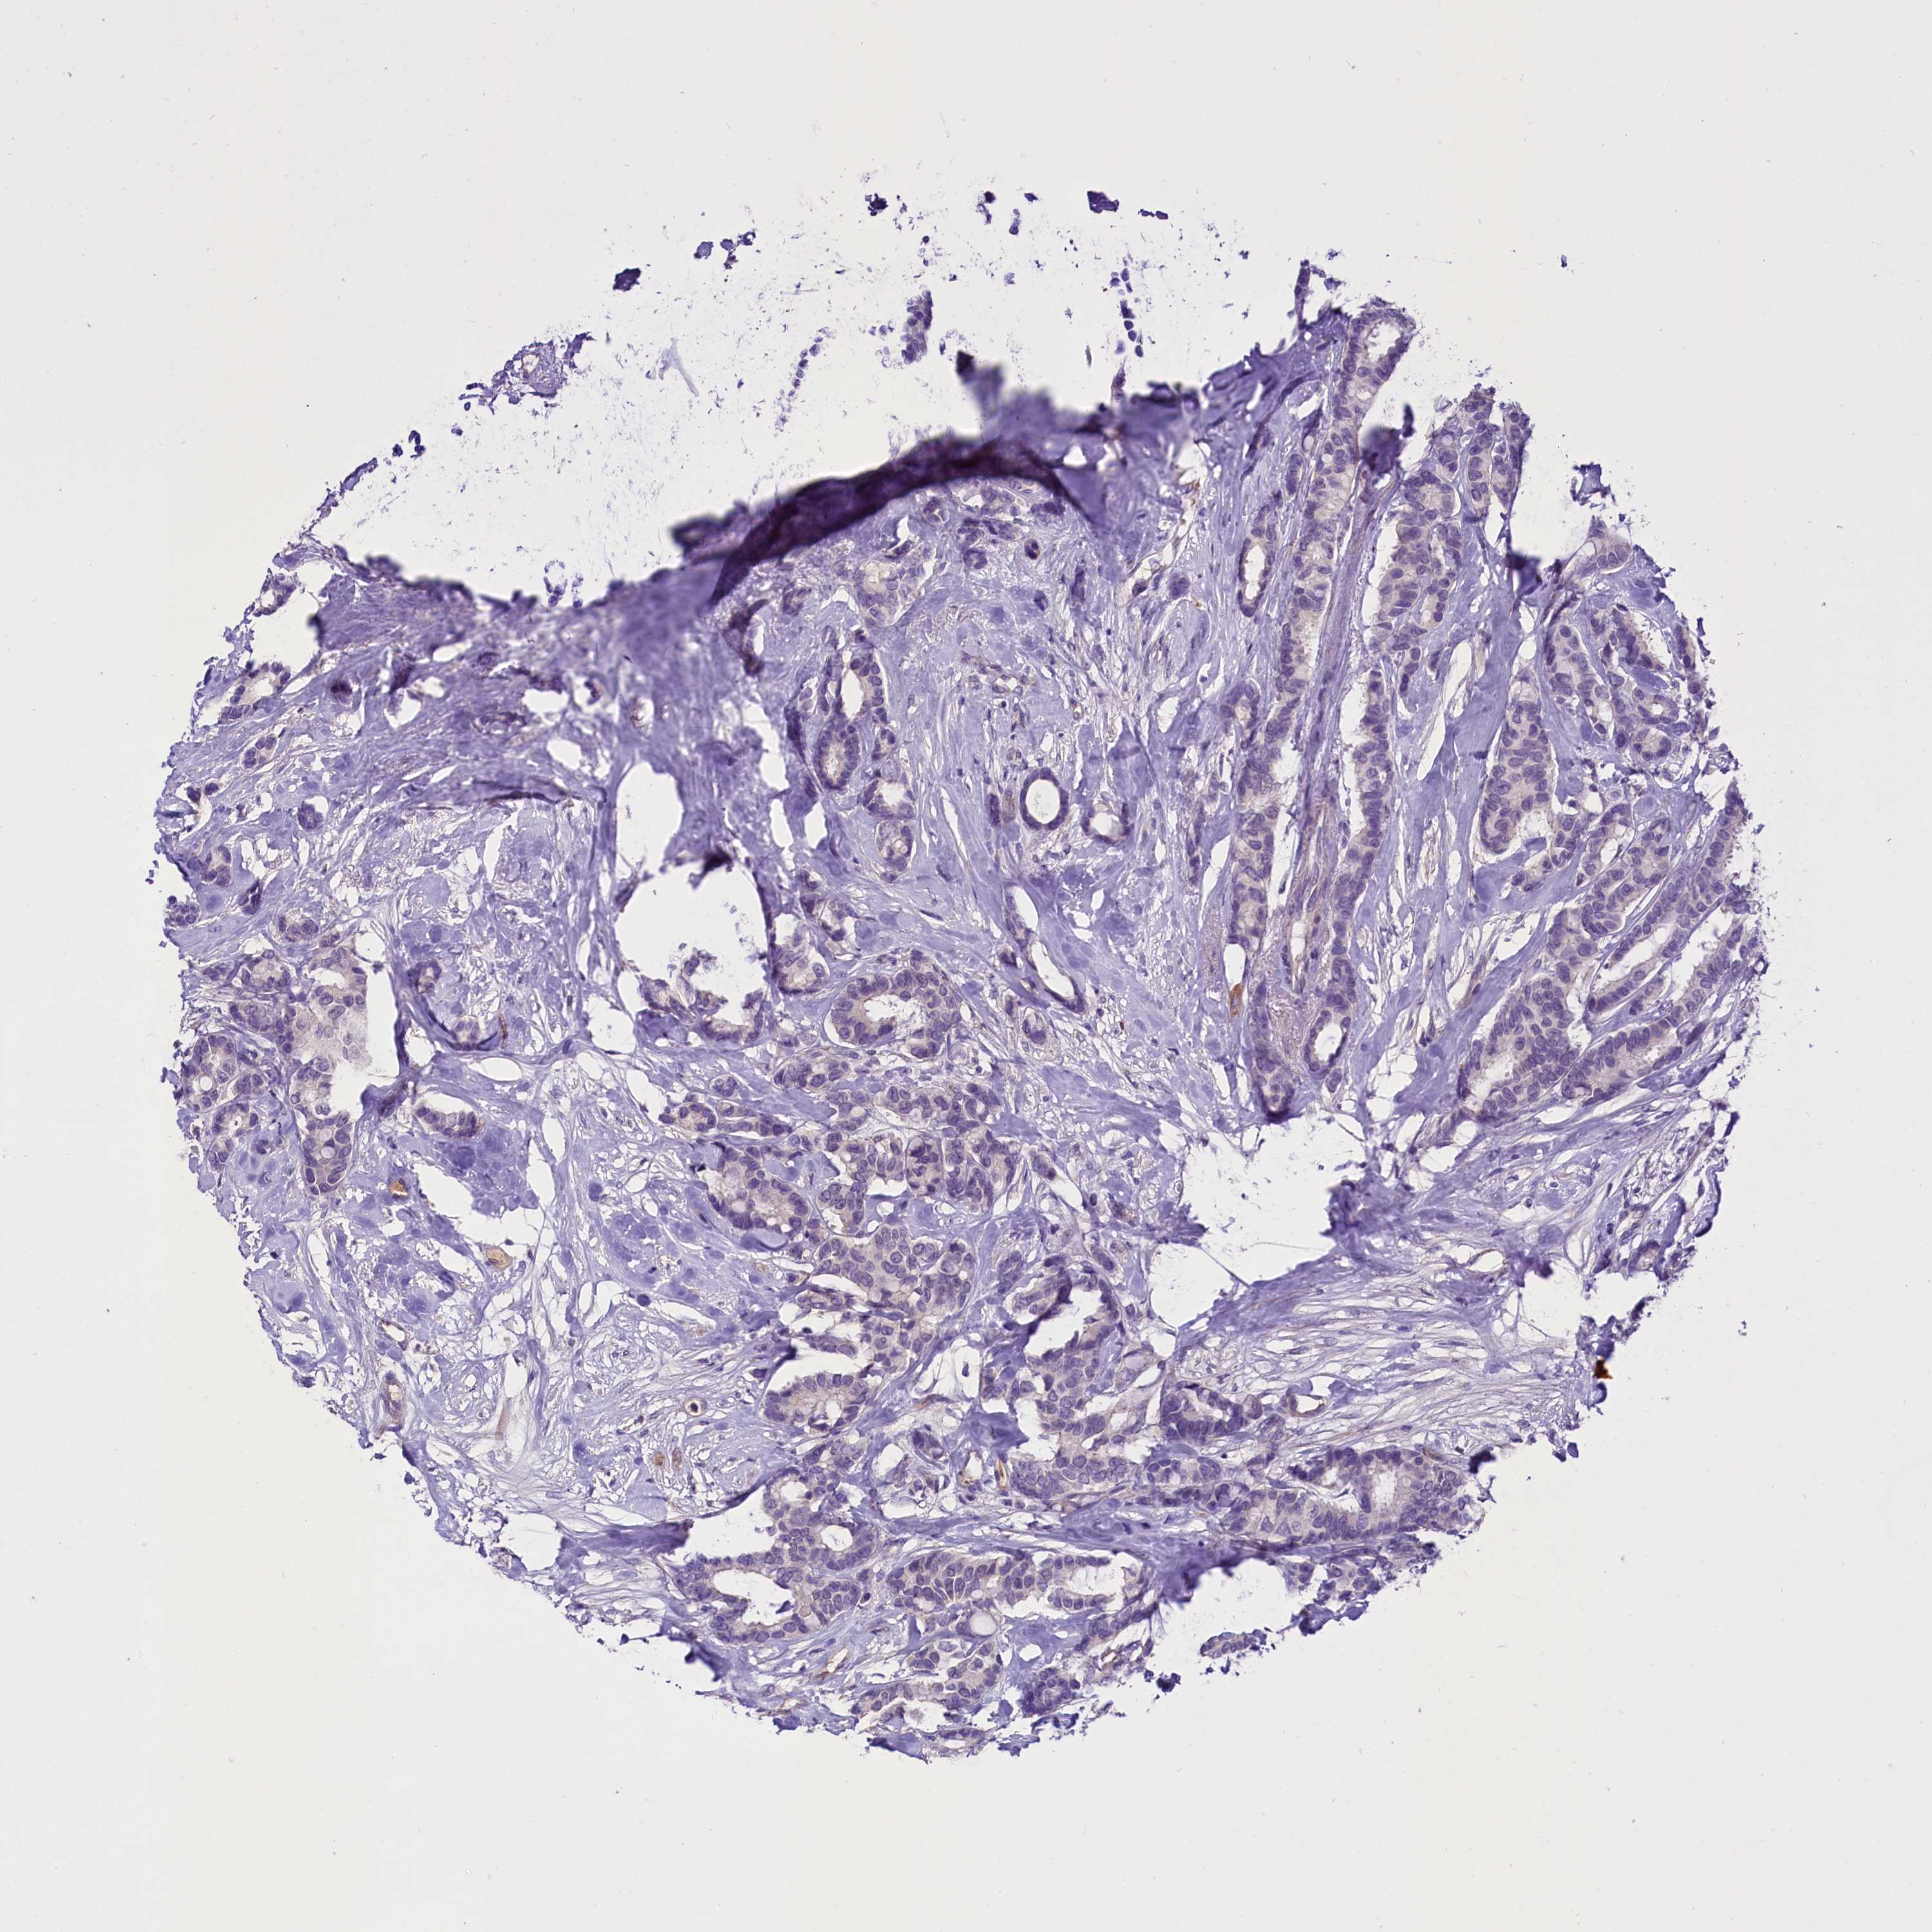

CANCER BREAST CANCER Show tissue menu

BRCA TCGA BRCA VALIDATION PROTEIN EXPRESSION

ANTIBODIES

AND

VALIDATION